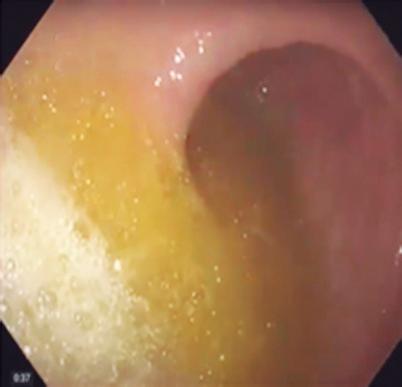

En primer lugar, la endoscopía proporciona información anatómica y mucosa crítica que contextualiza los hallazgos fisiológicos. La graduación de la esofagitis mediante la clasificación de Los Ángeles, la evaluación de EoE con biopsias sistemáticas y puntuación EREFS, la valoración de la válvula gastroesofágica y de la hernia hiatal, así como la identificación de signos endoscópicos sugestivos de acalasia, aportan elementos fundamentales para la interpretación integrada de los datos fisiológicos posteriores.8

En segundo lugar, la introducción de herramientas estructuradas de estratificación endoscópica de riesgo, como el Clinical Achalasia Risk Score (CARS), permite estimar la probabilidad de acalasia basándose en hallazgos endoscópicos reproducibles. El CARS incorpora la evaluación del contenido esofágico, la anatomía luminal, la resistencia a nivel de la UEG y los cambios mucosos relacionados con estasis, demostrando un excelente valor predictivo para acalasia cuando los puntajes superan los umbrales predefinidos.4, 5

La endoscopía continúa siendo la piedra angular en la evaluación esofágica debido a su capacidad para excluir malignidad, identificar la enfermedad mucosa y detectar una obstrucción mecánica. Sin embargo, hasta el 50 - 70% de los pacientes sometidos a una endoscopía digestiva alta por síntomas esofágicos no presentan anormalidades evidentes, lo que deja a los clínicos con escasa claridad diagnóstica y a los pacientes con síntomas persistentes.3 En estos casos son necesarias las pruebas funcionales esofágicas -manometría de alta resolución (MAR), monitoreo ambulatorio del reflujo y esofagograma baritado- para establecer un diagnóstico. Lamentablemente, estos estudios suelen realizarse semanas o meses más tarde, requieren derivación a centros especializados y están limitadas por una tolerancia subóptima y una proporción no despreciable de estudios incompletos.2, 3

tas como la planimetría FLIP y el monitoreo inalámbrico del pH (colocación de la capsula), proporcionando una evaluación en tiempo real de la motilidad esofágica, la dinámica de apertura de la unión esofagogástrica (UEG) y la carga de reflujo. Cuando se combinan con sistemas estructurados de estratificación endoscópica de riesgo, como el Clinical Achalasia Risk Score (CARS),4, 5 estas tecnologías permiten un enfoque diagnóstico de precisión integrado durante la endoscopía índice.